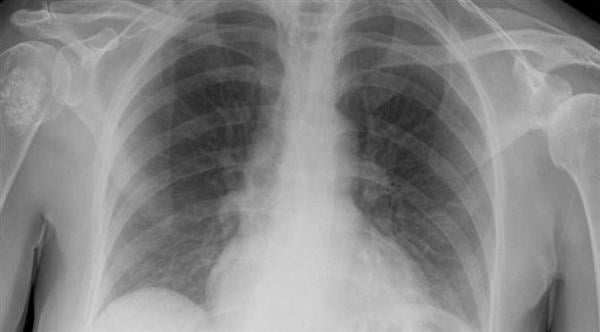

ويتم تشخيص التليف الرئوي بواسطة الأشعة السينية والأشعة المقطعية واختبار وظائف الرئة وفحوصات الدم والخزعة (أخذ عينة من نسيج الرئة).